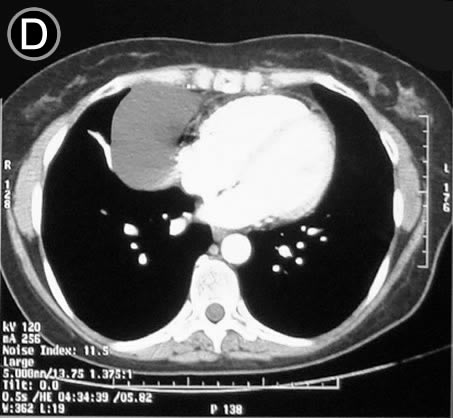

Corte Tomográfico D

Sección transversal mas inferior a la altura del cardias:

El corazón mantiene su conformación bien limitado.

la lesión se sitúa adosada al lado derecho del cardias.